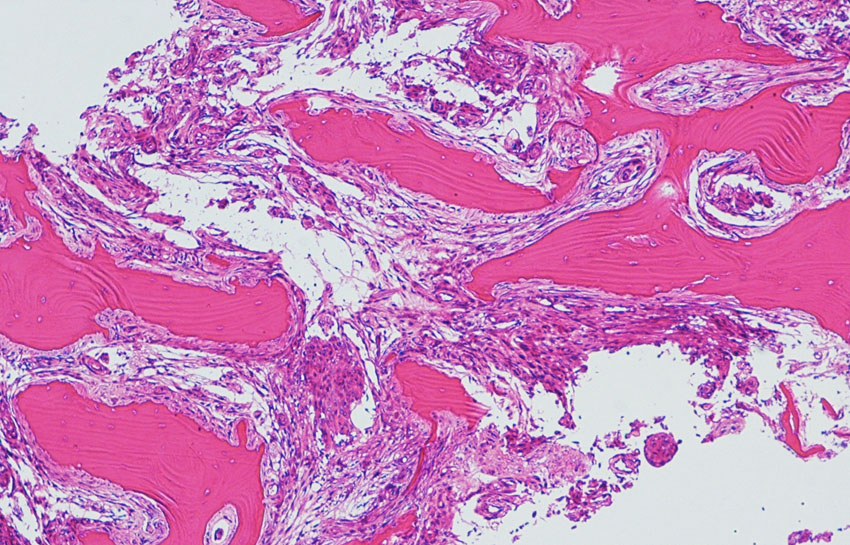

上矢状洞髄膜腫 superior sagittal sinus meningioma

手術直後の画像です。全部いっぺんに摘出するのは無理なので,まず前から80%くらいの腫瘍を摘出しました。肥厚した骨はチタンプレートで置き換えてあります。後頭部の上矢状洞内と大脳鎌に少し残りましたが,この6ヶ月後に2回目の開頭術をして全摘出しました。結果的にこの例では,上矢状洞を冠状縫合のあたりから,静脈洞交会まで壁ごと全部摘出しましたが,脳浮腫も何も生じませんでした。腫瘍の両側にある皮質静脈 cortical veinsを損傷しないことが肝要です。

右の病理像は,頭蓋骨浸潤している部分 ですが,骨破壊は良性髄膜腫に特徴的な骨内浸潤像です。この骨浸潤像は悪性像とはいえません。MIB-1は高いところで8%、低いところで3%程度です。